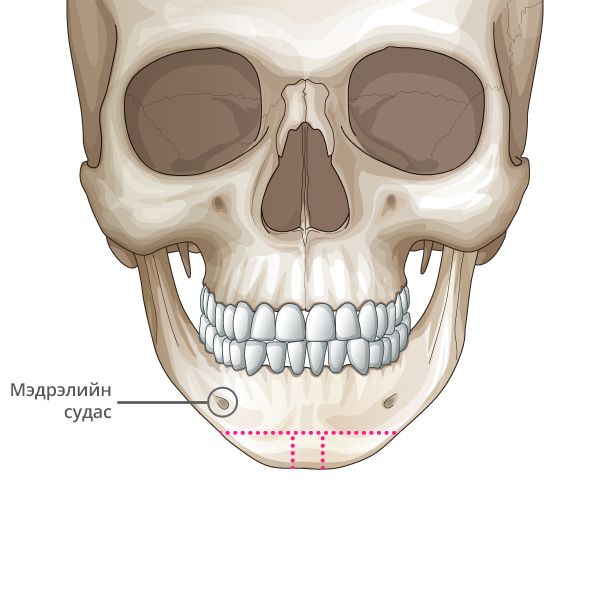

Мэдрэлийн судаснаас зайлсхийж, эрүүний төгсгөлд зүсэлт хийнэ.

Ясны гол хэсгээс тайралт хийж авна.

Зүсэлт хийгдсэн эрүүний хоёр талыг нийлүүлнэ.

Эрүүний ясыг нийлүүлж тогтоож өгнө.

Хоёр хажуу талд товойж харагдах ясны хэсгийг тайрна.